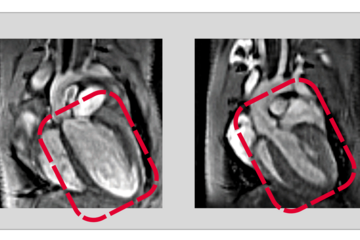

Während der Entwicklung des Embryos durchläuft das Herz kritische molekulare und strukturelle Veränderungen, die es für eine lebenslange Schwerstarbeit fit machen. Nach der Geburt stoppt die Vermehrung der Herzzellen und es werden zusätzliche Zellkerne gebildet. Gleichzeitig werden die kontraktilen Einheiten, die Sarkomere, innerhalb der Herzmuskelzellen steifer. Störungen oder Fehler in diesem Reifungsprozess sind häufig mit angeborenen Herzfehlern verbunden. Um diese zu verhindern, ist ein detailliertes Verständnis der molekularen Mechanismen, die der Reifung von Herzzellen zugrunde liegen, unerlässlich.

„Zunächst haben wir Mäuse untersucht, denen genetisch nur einer der beiden Spleißfaktoren der RBPMS/RBPMS2-Familie fehlt. Bemerkenswerterweise zeigten die Mäuse trotz der Inaktivierung von RBPMS eine normale Herzentwicklung und normale Herzfunktion nach der Geburt“, sagt Shan Lin, Erstautor der Studie. Als Nächstes inaktivierte Shan auch RBPMS zusammen mit RBPMS2, was zu schweren Defekten bei der Herzentwicklung und dessen Funktion führte. „Die gleichzeitige Inaktivierung von RBPMS und RBPMS2 hat uns gezeigt, dass der Verlust eines Gens während der Herzentwicklung durch andere Gene kompensiert werden kann“, erklärt Lin.

Aber welche molekularen Prozesse werden durch Spleißproteine gesteuert? „Unsere Studien haben gezeigt, dass RBPMS und RBPMS2 eine Schlüsselrolle bei mehreren grundlegenden Prozessen der Herzentwicklung spielen”, so Lin. Die Gruppe entdeckte, dass RBPMS und RBPMS2 nicht nur die Bildung von Isoformen für Proteine des Sarkomers steuern, sondern auch die Bildung des Spindelapparats regulieren, der für die Zellteilung unerlässlich ist. „Wenn beide Proteine inaktiv sind, ist die Zellteilung gestört“, erklärt Lin.